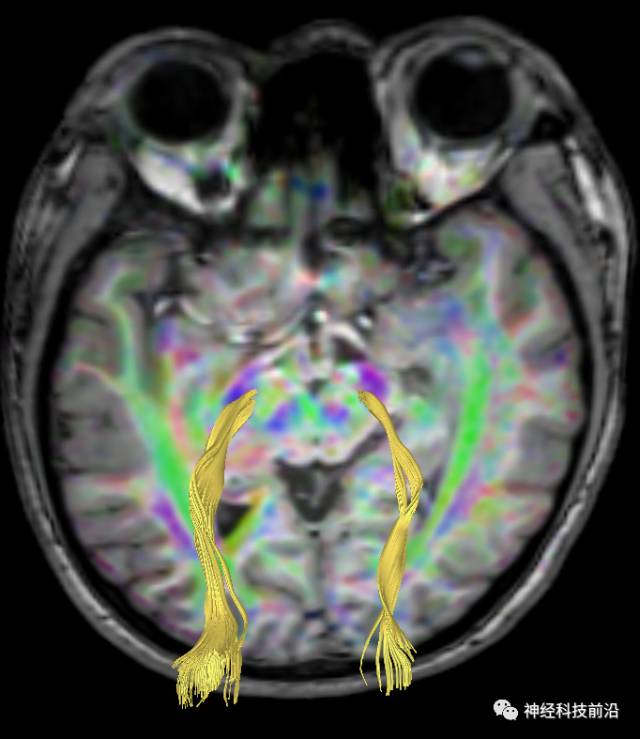

下面为皮质脑桥束的走形方位

皮质脑桥束与脑干高信号(黄色)纤维束